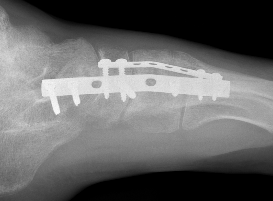

ORIF

Bridge plating

Cuboid plates

Severe comminution / lateral column shortening

- consider temporary distractor / external fixation to obtain length

- calcaneum to 4th / 5th metatarsal plate

- non-weight bearing until union then remove plates (typically 12 weeks)